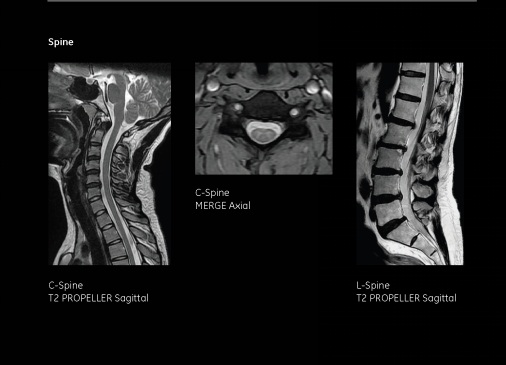

二、脊柱及脊髓

適應癥有:椎管內腫瘤、脊髓病變及損傷、顱底畸形、脊柱先天畸形、頸椎病、腰椎病、椎體病變(如椎體腫瘤、結核)、外傷等。椎管水成像可用于觀察椎管內占位、先天性變性病變。